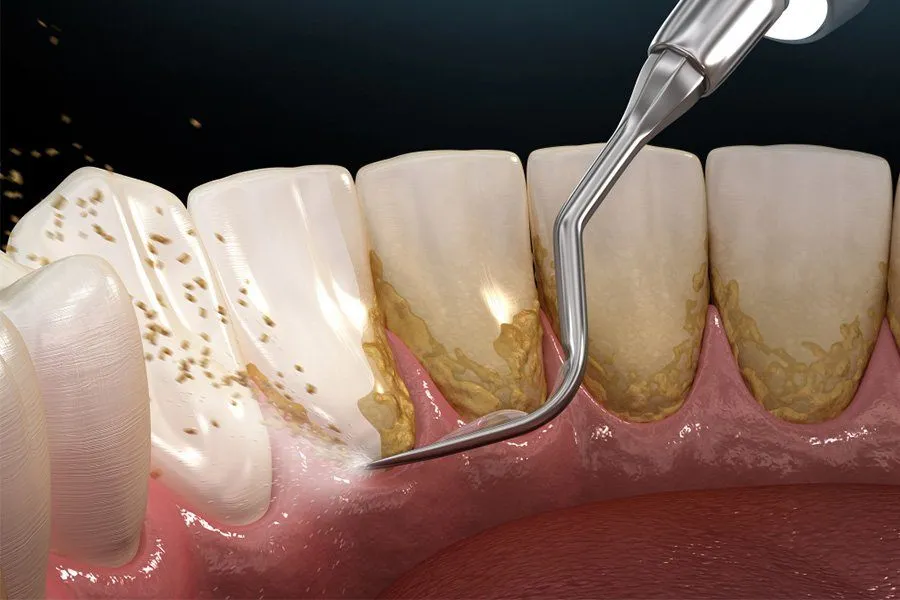

Bệnh nha chu là bệnh mà nhiều người đang gặp phải với trung bình 3 người thì 1 người bị. Bệnh này nếu không được điều trị

Viêm nướu là một trong những bệnh gây kích ứng, sưng đỏ phần nướu quanh chân răng. Người mắc phải không chỉ gây khó chịu mà còn